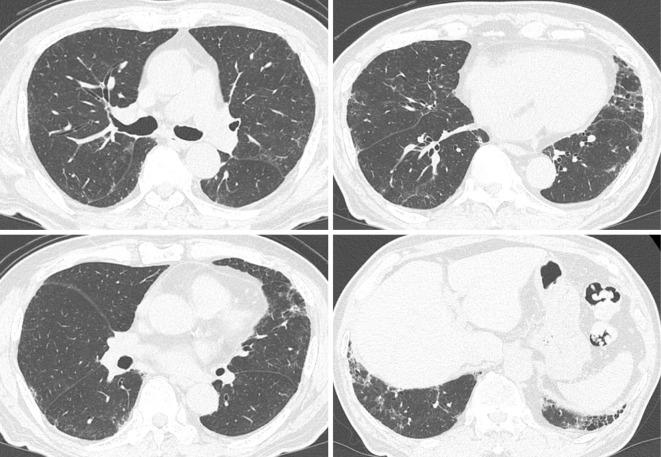

An 82-year-old Japanese man with idiopathic pulmonary fibrosis (IPF) experienced dyspnea after using a waterproofing spray in a closed room. He presented with hypoxemia and his chest computed tomography showed additive bilateral diffuse ground-glass attenuation on fibrosis, which was diagnostic of an acute exacerbation of IPF (AE-IPF). Combined treatment with high-dose corticosteroids and immunosuppressants were ineffective, and he later died of respiratory failure. Autopsy findings showed diffuse alveolar damage with honeycombing. His medical history and autopsy histopathology suggested AE-IPF caused by the inhalation of a waterproofing spray.

一位 82 岁的日本男性,患有特发性肺纤维化(IPF),在密闭房间内使用防水喷雾后出现呼吸困难。他表现出低氧血症,胸部计算机断层扫描显示纤维化的双侧弥漫性磨玻璃样混浊加重,这是特发性肺纤维化急性加重(AE-IPF)的诊断依据。大剂量皮质类固醇和免疫抑制剂联合治疗无效,后来他因呼吸衰竭而死亡。尸检结果显示弥漫性肺泡损伤伴蜂窝肺。他的病史和尸检组织病理学提示 AE-IPF 是由吸入防水喷雾引起的。